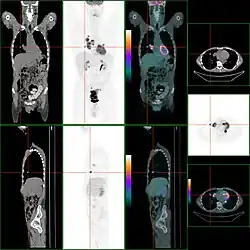

Zum Einsatz der Positronen-Emissions-Tomographie (PET) gibt es unterschiedliche Auffassungen. Entgegen mehreren internationalen Publikationen, die zeigen konnten, dass der Einsatz der PET/CT mit Fluordesoxyglucose signifikanten Einfluss auf die Stadieneinteilung hatte und gängigen Verfahren wie CT oder MRT in der Diagnose von Lymphknotenbefall oder Metastasen überlegen ist, sieht die aktuelle deutsche Leitlinie der Fachgesellschaften keinerlei Stellenwert in der Primärdiagnostik.[33] Die Verfasser der Leitlinie kritisieren hierbei die fehlende ausreichende Qualität der zugrunde liegenden Studien, ein Kritikpunkt, den das Institut für Qualität und Wirtschaftlichkeit im Gesundheitswesen, IQWIG bereits 2011 geäußert hatte.

Eine Kostenübernahme durch die gesetzlichen Krankenkassen ist für PET jedoch noch nicht möglich, während private Krankenversicherungen die Kosten teilweise tragen.

Bei fraglicher oder nachgewiesener Lebermetastasierung kann der Einsatz von PET für die Patienten von Nutzen sein, Empfehlungsgrad 0, Level of Evidence 2b.